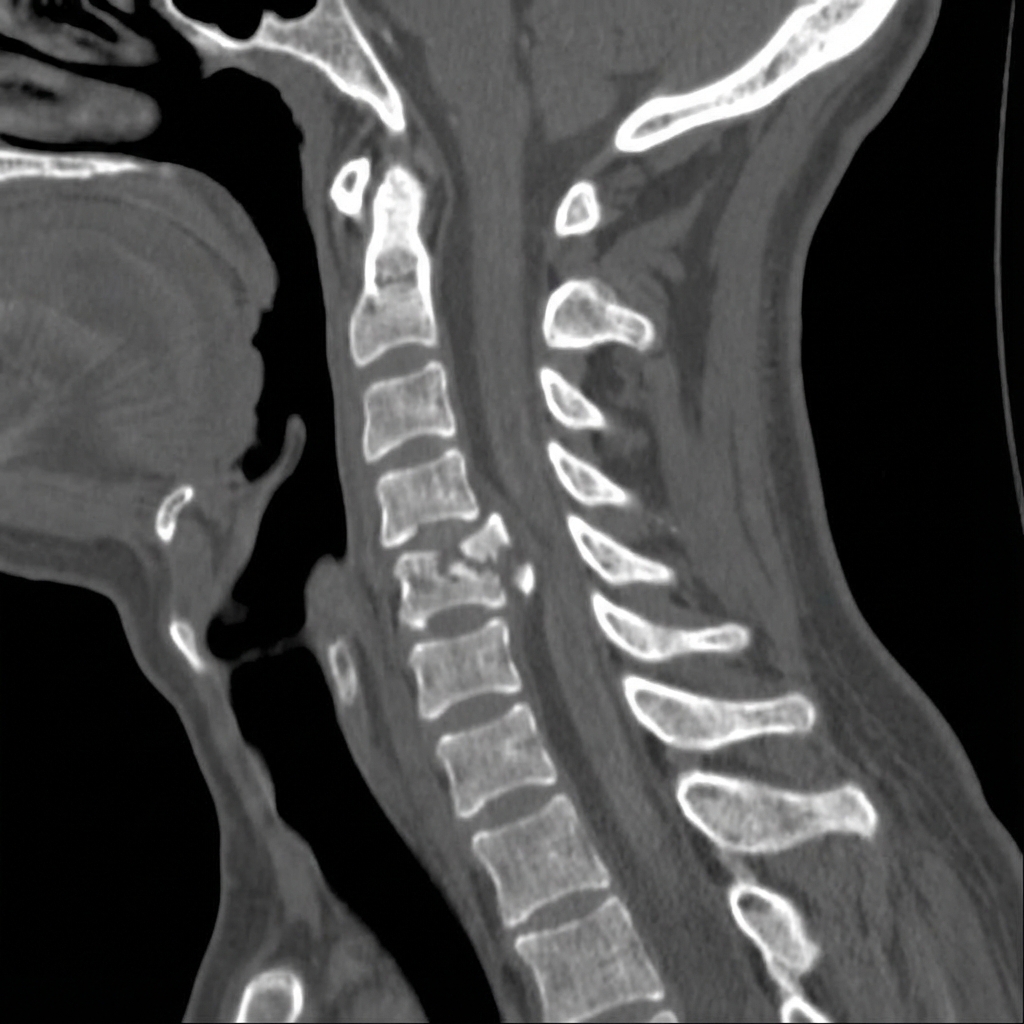

Sagittal and axial CT images demonstrating a C5 burst fracture with loss of vertebral body height, retropulsed posterior wall fragment causing canal compromise of approximately 50%. The posterior ligamentous complex appears intact on CT. MRI shows cord compression with edema. This represents a subaxial cervical injury requiring SLIC scoring for treatment decision.

Describe the imaging findings and apply the SLIC classification.